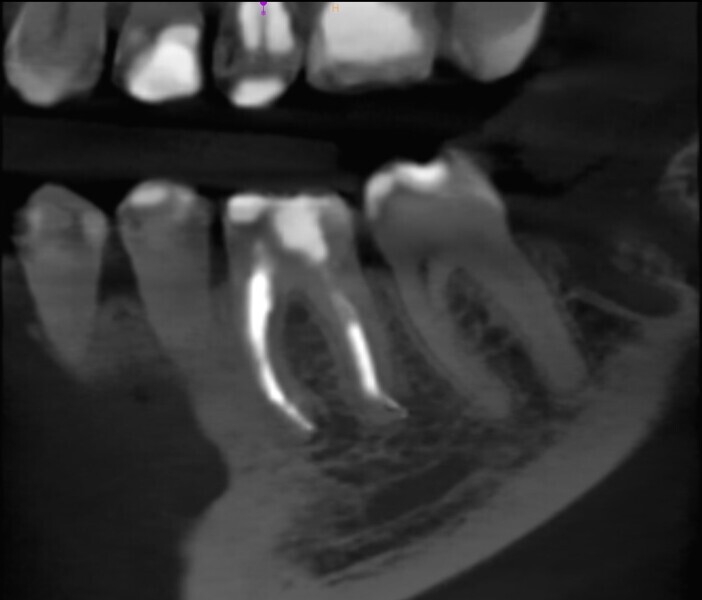

Fig. 2: Pre-op CBCT scan. Broken file far beyond the canal curvature.

Fig. 3: Pre-op CBCT scan. Tip of the broken file located below the junction of the mesiobuccal and mesiolingual canals.

The periapical radiograph and the CBCT scan revealed that the file had broken far beyond the curvature in the mesiobuccal canal and below the junction with the mesiolingual canal. Also, a periapical lesion was visible around the apices of the mesial and distal roots (Figs. 1–3). The length of the file was approximately 5 mm. Bypassing the file through the mesiolingual canal would have been a risky procedure because it may have caused the fracture of the second instrument and the obturation may also have been very challenging. Thanks to SWEEPS technology and a bioceramic sealer, an alternative approach could be taken. After administering anaesthesia and placing a dental dam, the temporary restoration was removed (Figs. 4 & 5). The pulp chamber was rinsed with 5.25% sodium hypochlorite and the irrigant activated with ultrasonics. After cleaning the chamber of the tooth, the dental dam and clamp were rinsed with water and dried and flowable dental dam was placed to seal the tooth and enlarge the space in the pulp chamber for the laser-activated irrigation (Fig. 6). Activation was performed with the SkyPulse laser (Fotona). The AutoSWEEPS mode was chosen. The power of activation was set to 1 W. The flat SWEEPS 300/20 fibre tip was used (Fig. 7). The tip was placed slightly below the orifice of the mesiobuccal canal for the majority of the irrigation with sodium hypochlorite. After 120 seconds of activation with sodium hypochlorite, the tip was placed in the pulp chamber to activate the sodium hypochlorite in all the canals simultaneously for 30 seconds. This procedure was continued for 30 minutes. Only the distal canal was shaped with rotary files, up to size 40/.04. Both mesial canals remained the same size as they were before the file broke during the primary treatment. Finally, the canals were flushed with EDTA activated with AutoSWEEPS at a power of 0.4 W, and sodium hypochlorite was activated for three cycles with AutoSWEEPS at a power of 0.6 W and with a 30-second break for the resting phase. The irrigant flow between the mesiobuccal and mesiolingual canals was rapid, indicating that obturation could be performed.